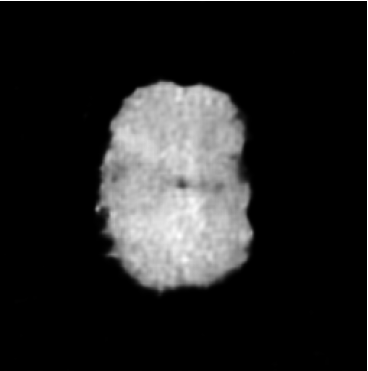

While ACAT revolves around generating counterfactuals, its primary strength lies in accurately identifying pathological regions, which are subsequently employed in a classification pipeline. On the other hand, it falls short in producing credible counterfactual examples, an issue we aim to address in this study. An illustration of this phenomenon is depicted in Figure 2, where we can observe how ACAT is able to generate a saliency map that approximately identifies the pathological region (e, bottom row). However, in the counterfactual example, the lesion remains visible (e, top row). In contrast, our approach not only refines the saliency map but also generates a counterfactual image where the pathology is completely eliminated (f).

4.3 Counterfactual Examples

In Figures 2 and 4 we display examples of healthy images and anomaly maps obtained with the different approaches. We can observe that f-Ano GAN is not able to generate credible counterfactuals and generally produces images of poor quality and unrealistic appearance. On the other hand, the approaches based on diffusion models are able to create more high-quality results. However, the ones obtained with CG and CFG seem to present some artifacts, which may not only impact the realism of the counterfactual examples but also the precision of the anomaly maps obtained from them. In order to better quantify the capability of these methods to accurately segment pathological areas, we compute the Dice scores of the anomaly maps they generate.